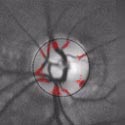

Here are retina images from twins / Ci-dessous deux rétines de jumeaux:

A kind of (circular) barcode is extracted from the pattern of blood vessels, which is stored for further comparison with a new retina image.

Une sorte de code à barres (circulaire) est extrait du réseau vasculaire, qui est stocké afin de permettre plus tard une comparaison avec une nouvelle image de rétine.

First the intensity profile is extracted, then a circular scan is performed to locate blood vessels.

Les lignes de plus fortes intensités sont d'abord extraites, puis un scan circulaire permet d'identifier la localisation des vaisseaux sanguins.